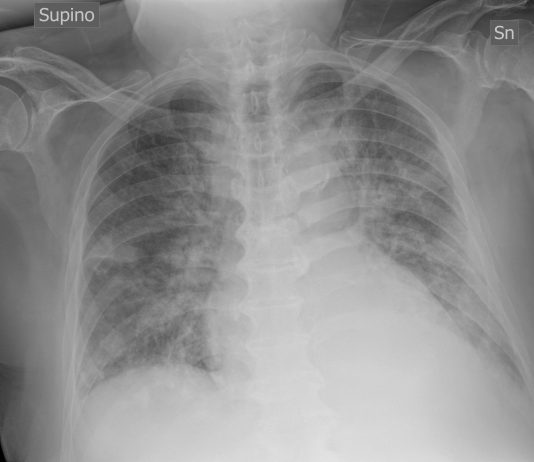

Pezzotti S., Botti P., Perotti V., Bnà C.Unità complessa di Radiologia - Istituto Ospedaliero Fondazione Poliambulanza (Brescia)Paziente donna di 47aa, accesso in PS in data 10/03/2020 per febbre e dispnea.APR: ipertensione arteriosa, obesità (esiti di intervento di chirurgia bariatrica)Tampone positivo per Covid-19.

RX torace...